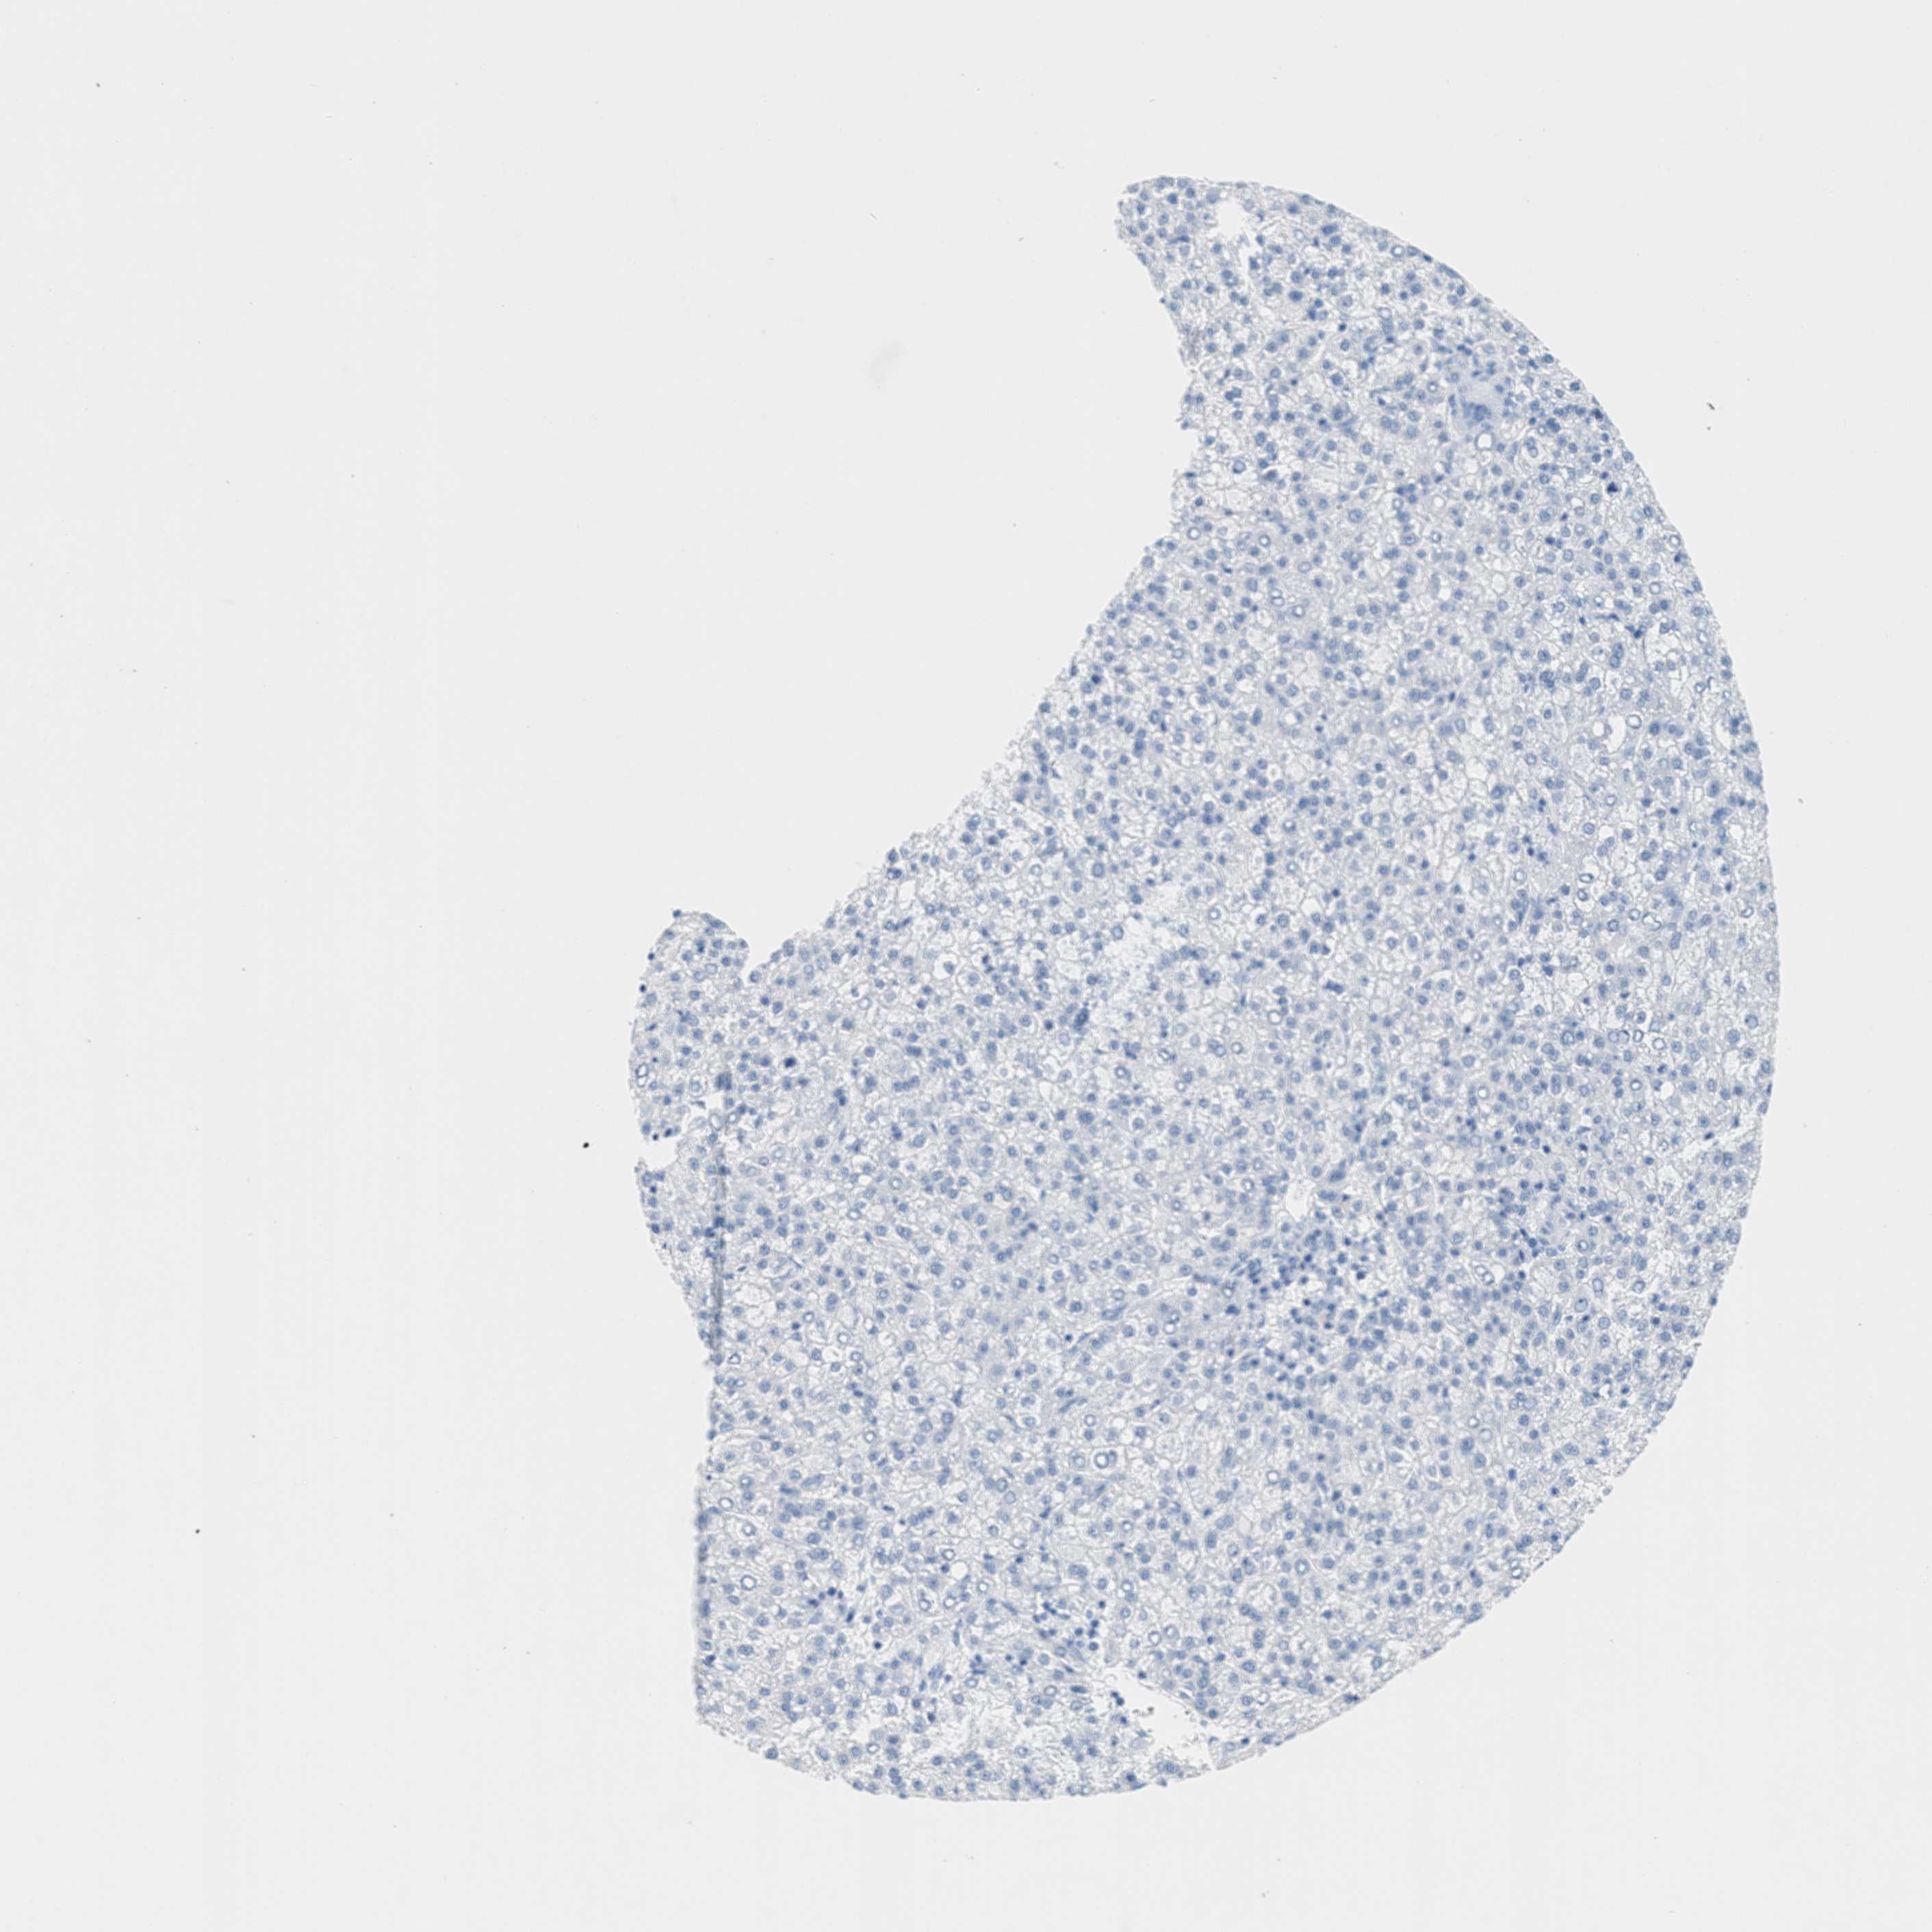

LIVER CANCER - Protein expressioni

A mouse-over function shows sample information and annotation data. Click on an image to view it in a full screen mode. Samples can be filtered based on level of antibody staining by selecting one or several of the following categories: high, medium, low and not detected. The assay and annotation is described here.

Note that samples used for immunohistochemistry by the Human Protein Atlas do not correspond to samples in the TCGA dataset.

Antibody stainingi

Antibody staining in the annotated cell types in the current human tissue is reported as not detected, low, medium, or high, based on conventional immunohistochemistry profiling in selected tissues. This score is based on the combination of the staining intensity and fraction of stained cells.

Each image is clickable and will lead to virtual microscopy that enables deeper exploration of all samples and also displays staining intensity scores, fraction scores and subcellular localization as well as patient and tissue information for each sample.

Antibody HPA017338

Staining

High

Medium

Low

Not detected

Intensity

Strong

Moderate

Weak

Negative

Quantity

>75%

75%-25%

<25%

None

Location

Nuclear

Cytoplasmic/membranous

Cytoplasmic/membranous,nuclear

Carcinoma, Hepatocellular, NOS

Cholangiocarcinoma